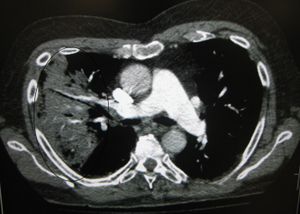

CT 스캔은 불확실한 경우 추가 정보를 제공할 수 있으며,[72] 흉부 방사선 사진이 불분명한 경우(예: 만성 폐쇄성 폐 질환에서 숨겨진 폐렴) 더 자세한 정보를 제공할 수 있다. 치료에 반응하지 않는 사람들의 폐색전증과 진균성 폐렴을 배제하고, 폐농양을 검출하는 데 사용될 수 있다.[78] 그러나 CT 스캔은 비용이 더 비싸고, 방사선량이 더 높으며, 병상 옆에서 시행할 수 없다.[78]